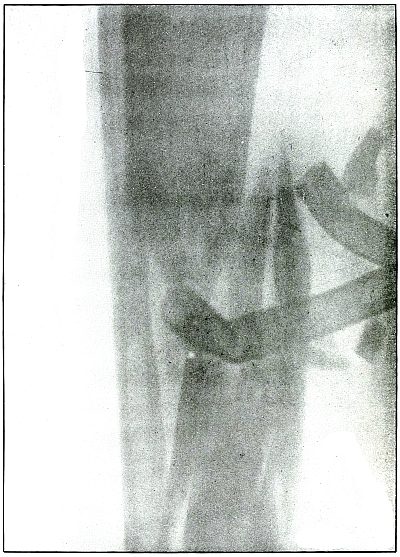

[Pg 118]

Plate 54.

[Pg 119]

Rifle—Plate 54.

LOWER EXTREMITY.

Gunshot Fracture of the Lower End of the Shaft of the Femur.

The course of the bullet was anteroposterior through the axis of the

femur. Several large fragments which were not displaced were separated

by the force of impact. The separation of the fragments and the

overriding of the ends of the proximal and distal large fragments were

due to bearing bodily weight or to muscular contraction.

The projectile causing the wound was moving with the velocity of mid

range. The wound of exit was not lacerated.

The emergency treatment is antiseptic dressing and temporary splint

immobilization. Permanent dressing, with extension and lateral

compression, is the rule.

Infection in such cases is frequent owing to lack of facilities for

proper dressing on the field.

Results in saving life and limb are generally good.

[Pg 120]